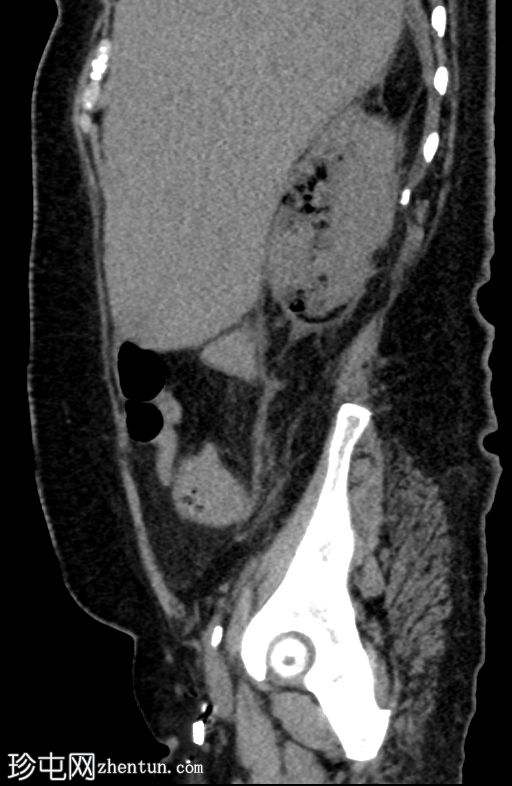

冠状位

平扫

肾实质内可见多个气体囊,主要累及右肾中部和下极。

肾周脂肪组织中度炎症性改变,并可见条索状肾周积液。

气体未延伸至肾盂或输尿管。

无肾积水。

少量微小的非梗阻性肾结石(砂砾)。